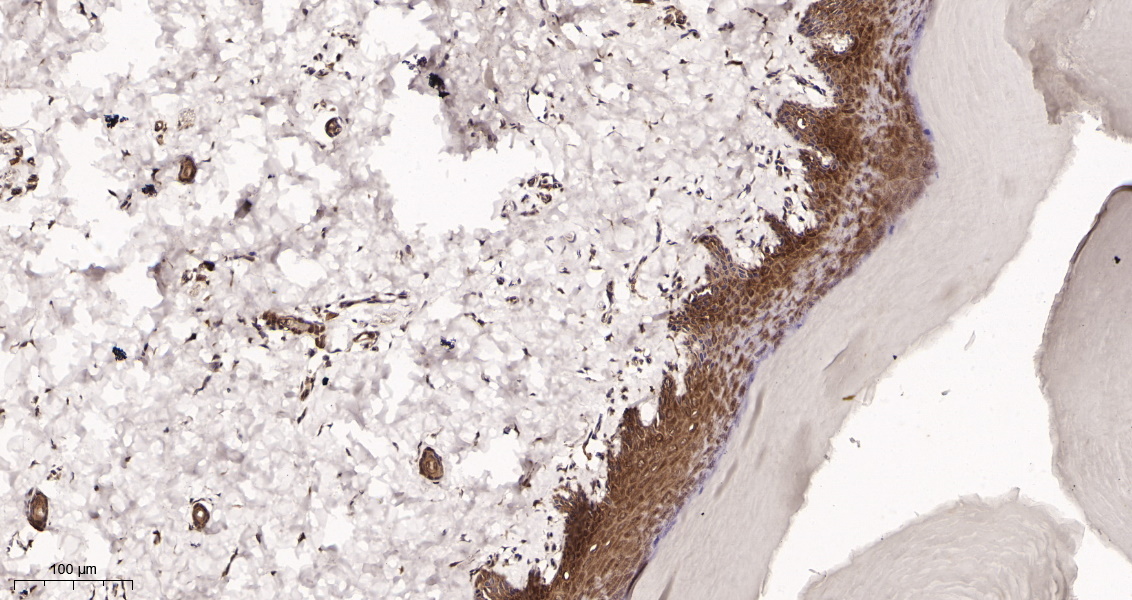

产品名称Collagen III (2X2) Rabbit Monoclonal Antibody

基因名称COL3A1

蛋白名称Collagen alpha-1(III) chain

推荐应用WB,IHC-P,IF-P,IF-F,IF-ICC,IP,ELISA

反应种属Human,Mouse,Rat

稀释度IHC-P 1:20-100,WB 1:1000-5000,IF-P/IF-F/IF-ICC 1:200-1000,ELISA 1:5000-20000,IP 1:50-200

背景介绍collagen type III alpha 1 chain(COL3A1) Homo sapiens This gene encodes the pro-alpha1 chains of type III collagen, a fibrillar collagen that is found in extensible connective tissues such as skin, lung, uterus, intestine and the vascular system, frequently in association with type I collagen. Mutations in this gene are associated with Ehlers-Danlos syndrome types IV, and with aortic and arterial aneurysms. Two transcripts, resulting from the use of alternate polyadenylation signals, have been identified for this gene. [provided by R. Dalgleish, Feb 2008].

信号通路Focal adhesion;ECM-receptor interaction.

功能disease:Defects in COL3A1 are a cause of Ehlers-Danlos syndrome type 3 (EDS3) [MIM:130020]; also known as benign hypermobility syndrome. EDS is a connective tissue disorder characterized by hyperextensible skin, atrophic cutaneous scars due to tissue fragility and joint hyperlaxity. EDS3 is a form of Ehlers-Danlos syndrome characterized by marked joint hyperextensibility without skeletal deformity.,disease:Defects in COL3A1 are a cause of susceptibility to aortic aneurysm abdominal (AAA) [MIM:100070]. AAA is a common multifactorial disorder characterized by permanent dilation of the abdominal aorta, usually due to degenerative changes in the aortic wall. Histologically, AAA is characterized by signs of chronic inflammation, destructive remodeling of the extracellular matrix, and depletion of vascular smooth muscle cells.,disease:Defects in COL3A1 are the cause of Ehlers-Danlos syndrome type 4 (EDS4) [MIM:130050]. EDS is a connective tissue disorder characterized by hyperextensible skin, atrophic cutaneous scars due to tissue fragility and joint hyperlaxity. EDS4 is the most severe form of the disease. It is characterized by the joint and dermal manifestations as in other forms of the syndrome, characteristic facial features (acrogeria) in most patients, and by proneness to spontaneous rupture of bowel and large arteries. The vascular complications may affect all anatomical areas.,function:Collagen type III occurs in most soft connective tissues along with type I collagen.,online information:Collagen type III alpha-1 chain mutations,online information:Type-III collagen entry,PTM:O-linked glycan consists of a Glc-Gal disaccharide bound to the oxygen atom of a post-translationally added hydroxyl group.,PTM:Proline residues at the third position of the tripeptide repeating unit (G-X-Y) are hydroxylated in some or all of the chains.,similarity:Belongs to the fibrillar collagen family.,similarity:Contains 1 VWFC domain.,subunit:Trimers of identical alpha 1(III) chains. The chains are linked to each other by interchain disulfide bonds. Trimers are also cross-linked via hydroxylysines.